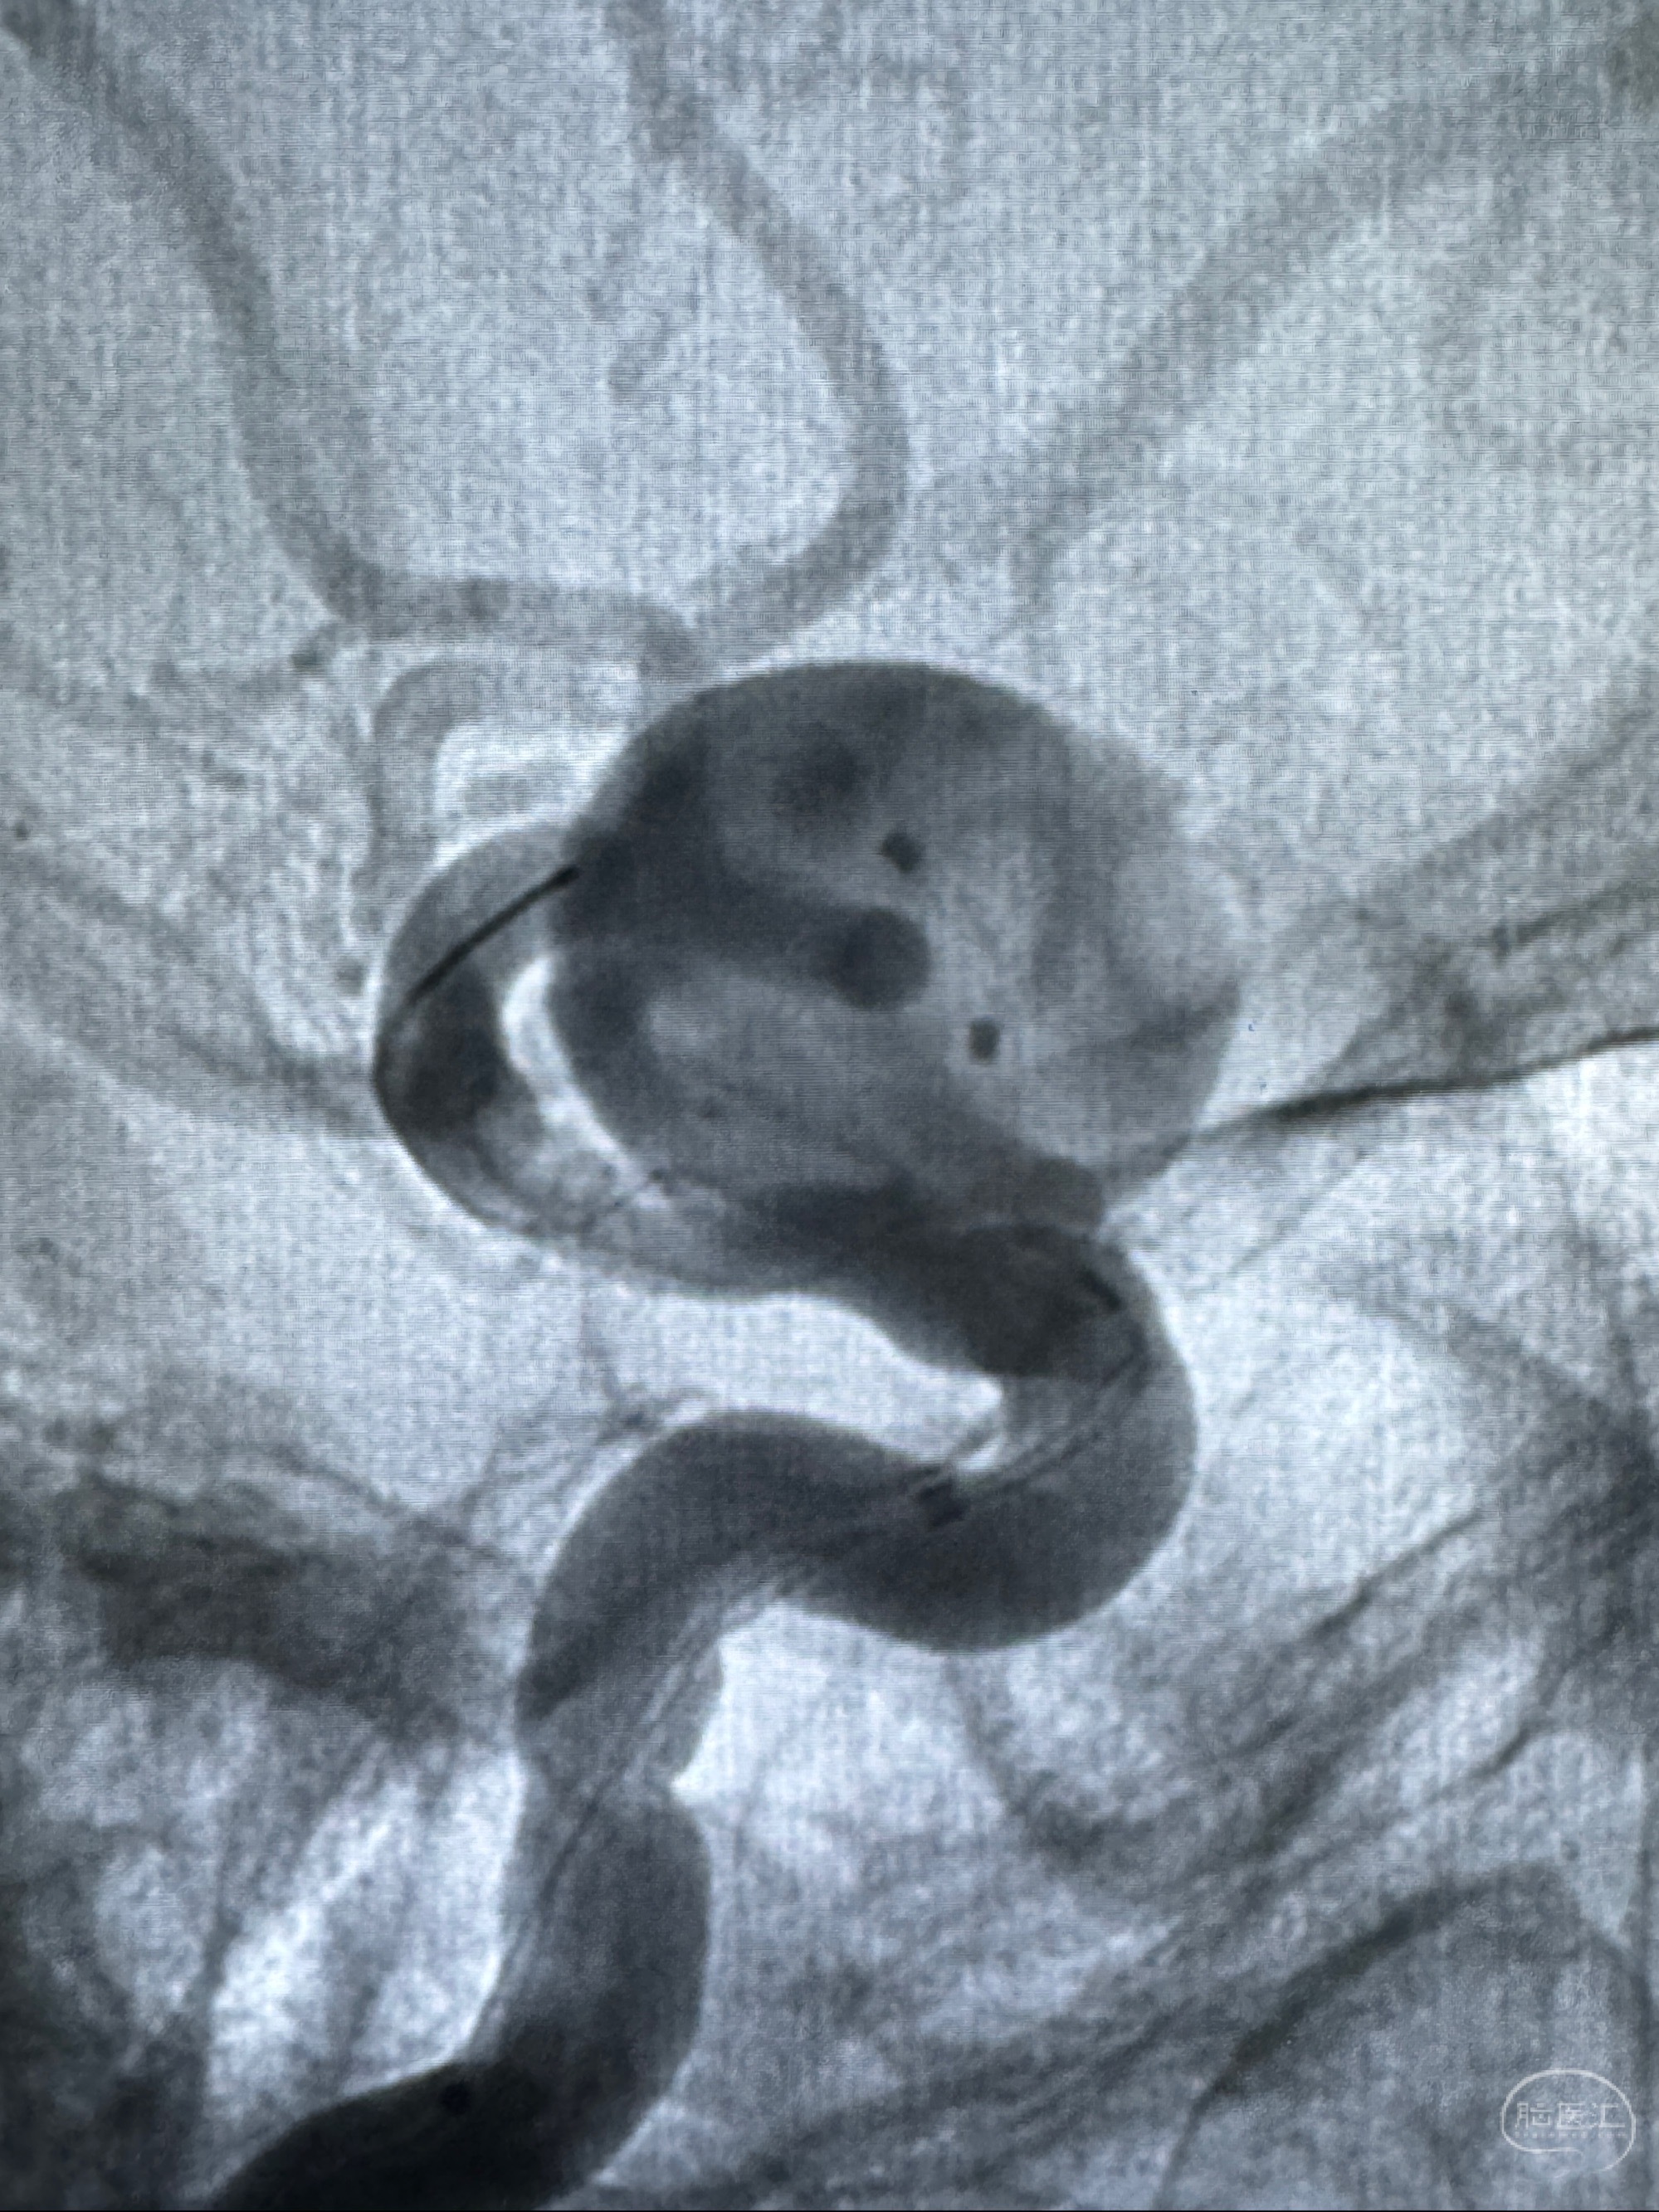

观察动脉瘤腔内的血流动力学情况

造影显示支架贴壁情况

再次造影确认支架贴壁情况